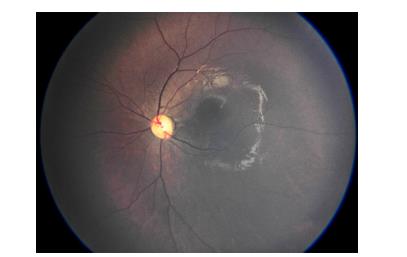

图4 正常成年人右眼UWFFA

Figure 4 Fundus image of the right eye of a normal adult using UWFFA

20221226095307_0523.jpg